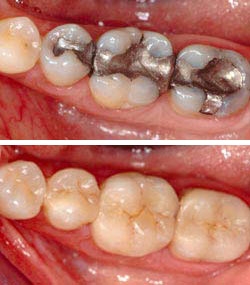

Inlays & Onlays